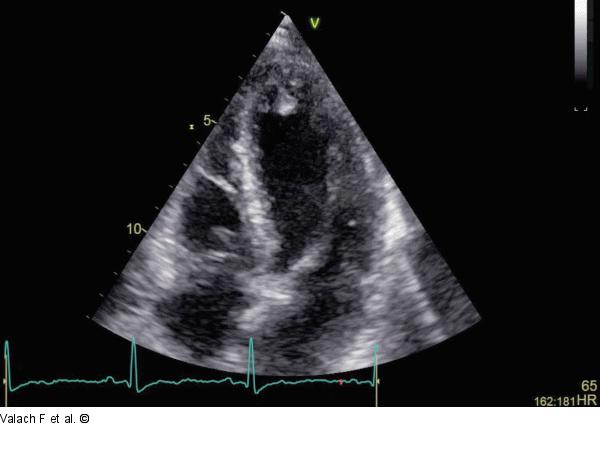

Abbildung 1: Apex Akut, ohne Thrombus |